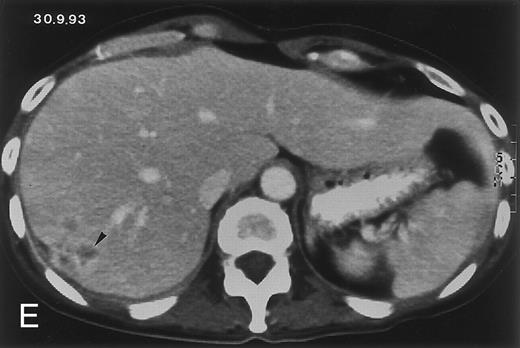

(D) On August 23, 15 days after the neutrophil count had dropped below 500/μL in the third chemotherapy cycle, focal liver lesions clearly decreased in size and number. (E) On September 30, 35 days after neutrophil recovery, multiple hepatic abscesses are seen (arrowhead). To show maximal extent of lesions the scan shown is at a slightly different level. (F) On June 16, 1994, 230 days after neutrophil recovery, the CT scan has normalized.